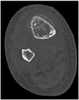

Chondral calcification

Periarticular calcification

Soft-tissue calcification